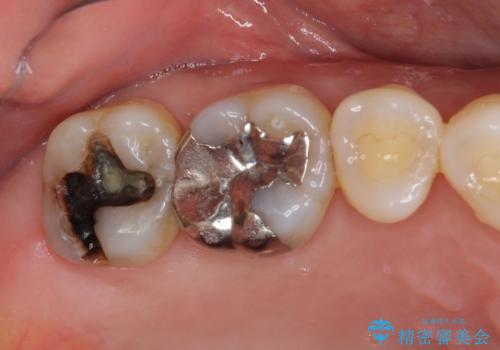

根管治療中の転院 奥歯のオールセラミック治療